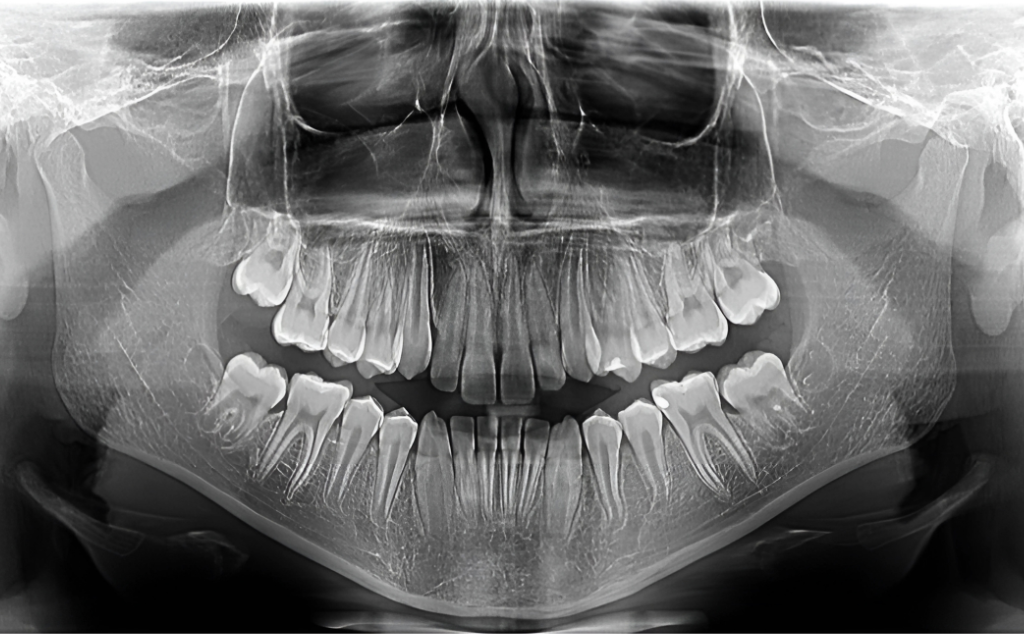

Descriere

OPG-ul este necesar în etapa de diagnostic pentru elaborarea planului de tratament, precum și pe parcursul sau la sfârșitul tratamentului, pentru a evalua evoluția acestuia.

Redă medicului stomatolog informații despre poziția și relația dinților, a mugurilor dentari încă neerupți, precum și detalii despre eventualele afecțiuni parodontale, sinusale și ale articulațiilor temporo-mandibulare.

Pentru ca imaginea radiologică să fie de bună calitate, trebuie să încercați să rămâneți nemișcat în poziția indicată de personalul specializat pe tot timpul expunerii.